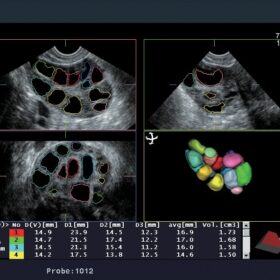

- Multi-follicle Volume (MFV)

RT-3D (4D)

Aloka ASU-1010 3D/4D Convex

Aloka ASU-1012 3D/4D Vaginal